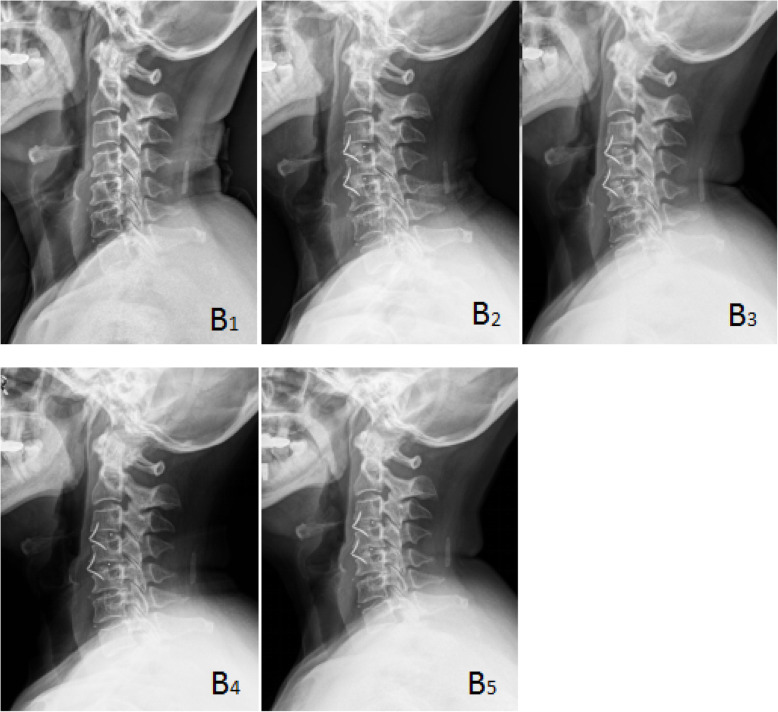

Fig. 2 .

A 66-year-old female in group B with cervical spondylotic radiculopathy. The preoperative VAS score, JOA score, and NDI score were 8, 14, and 33%, respectively, and the postoperative VAS score, JOA score, and NDI score were 1, 15, and 20%, respectively. The postoperative Odom score was “excellent”. Brantigan score: 3 points. B1 was preoperative X-ray plain film of the cervical spine, B2 was immediate X-ray plain film after operation, and B3, B4, and B5 were lateral plain film of cervical spine at 3, 6, and 9 months after operation, respectively